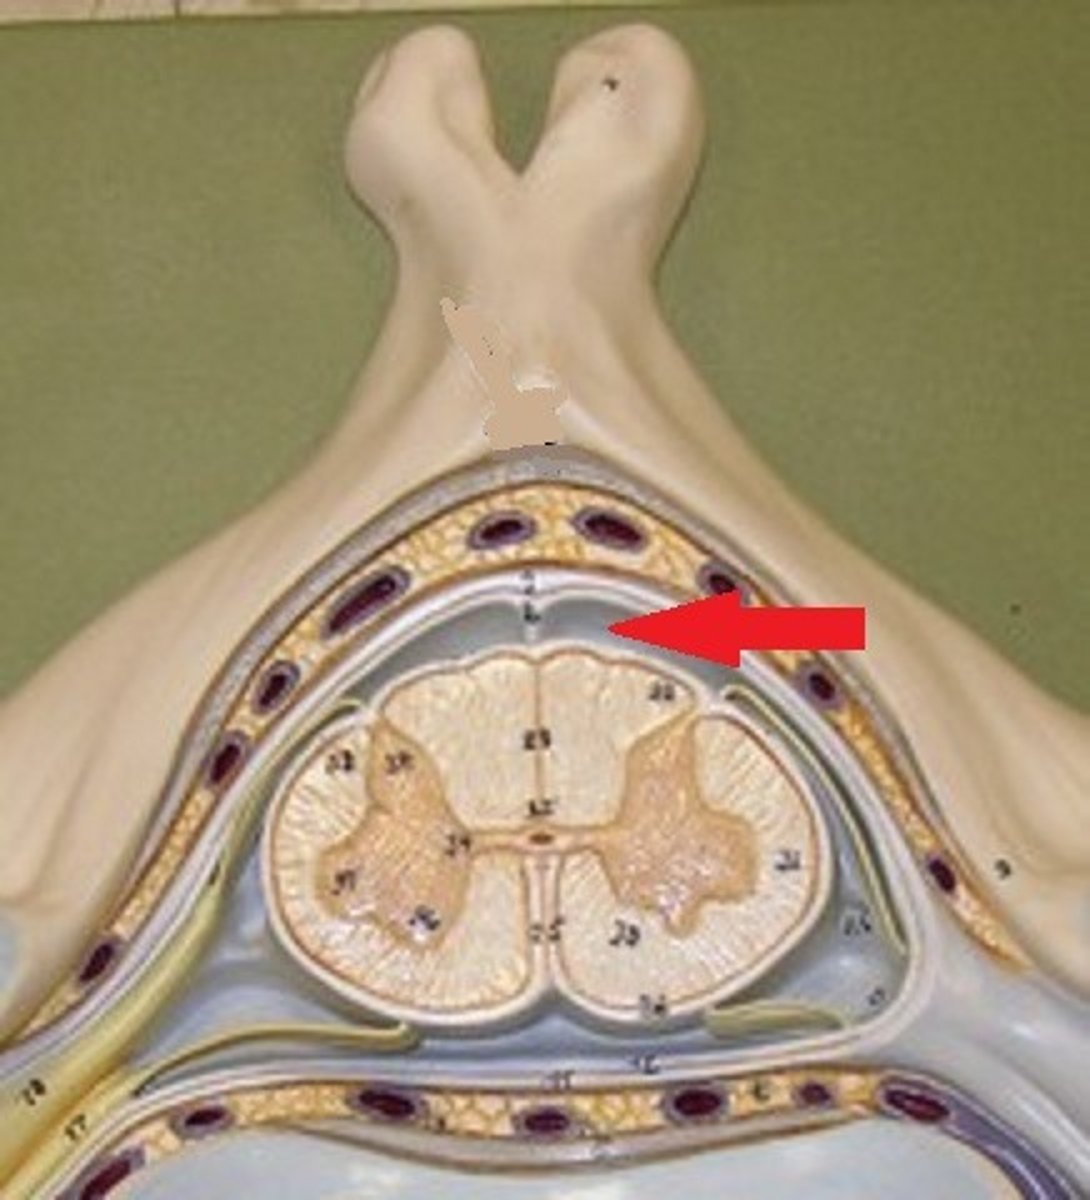

anterior (ventral) root (of spinal cord)

central canal (of spinal cord)

gray matter (of spinal cord)

posterior median sulcus

anterior median fissure

cauda equina

dorsal root ganglion (spinal)

posterior (dorsal) root (of spinal cord)

spinal nerve

white matter (of spinal cord)

arachnoid mater

dura mater

denticulate ligament

pia mater

subdural space

epidural space

subarachnoid space